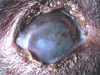

Mdx? Sequela?

Ciliary (Iridociliary) adenoma/carcinoma

Sequela = Glaucoma, hyphema, retinal detachment

DOGS >>>>>> cats

Most benign